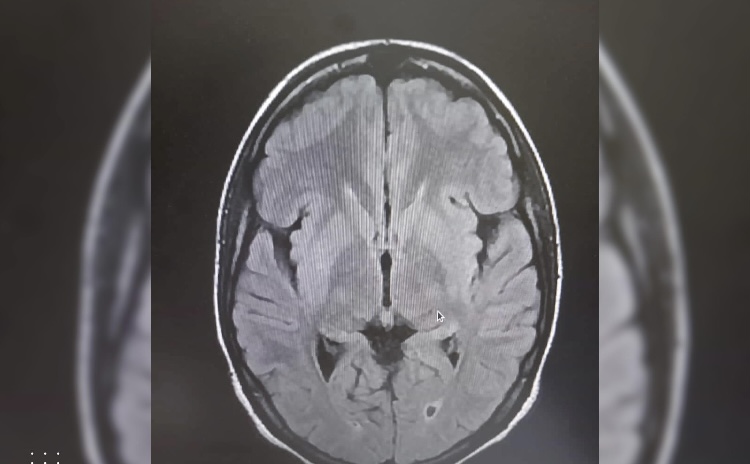

تمكن فريق طبي متخصص بالمستشفى العسكري، من تفتيت جلطة دماغية لمريضة في العشرينيات من العمر، بعد وصولها في حالة سكتة دماغية منتصف يوم الجمعة للحالات المستعجلة للمستشفى العسكري بنواكشوط.

وقد تمكن الفريق الطبي من تشخيص السكتة الدماغية قبل تجاوز الفترة الزمنية الضرورية (أربع ساعات ونصف)، وقام بتفعيل الإجراءات اللازمة للعلاج، الأمر الذي مكن من الحصول على الدواء الخاص لمثل هذه الحالات واستخدامه.

وتعد هذه المرة الأولى التي يتم فيها هذا النوع من العلاج، المتقدم و الحديث للسكتات الدماغية في المستشفيات الموريتانية.